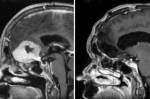

Хирург премахва голям мозъчен тумор през веждите

Хирург, работещ в Шотландия, разработи начин за отстраняване на мозъчен тумор с размер на ябълка през веждата на пациент, което... » повече